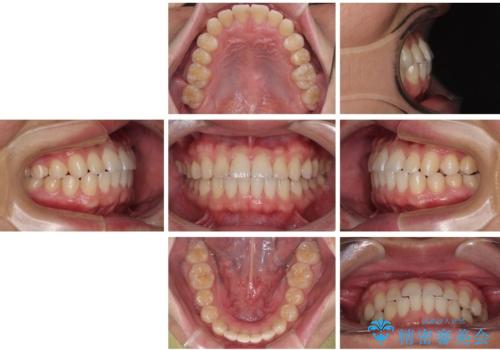

前歯のガタガタ・奥歯のかみ合わせ(シザーズバイト)を改善|1年半で完了したメタルブラケット矯正

今回ご紹介するのは、「前歯のガタガタ(叢生)」と「奥歯のかみ合わせ(シザーズバイト)」にお悩みでご来院された患者様の症例です。

・上顎左右の第二大臼歯が頬側へ転移し、シザーズバイト(scissors bite)の状態

・上顎左側第二小臼歯が90度捻転しており、噛み合わせに影響

**前歯のデコボコ(叢生)**が整い、歯列全体が美しく改善

シザーズバイトの奥歯も正常なかみ合わせに改善

捻転歯も回転が修正され、全体的に清掃性・咀嚼効率が向上